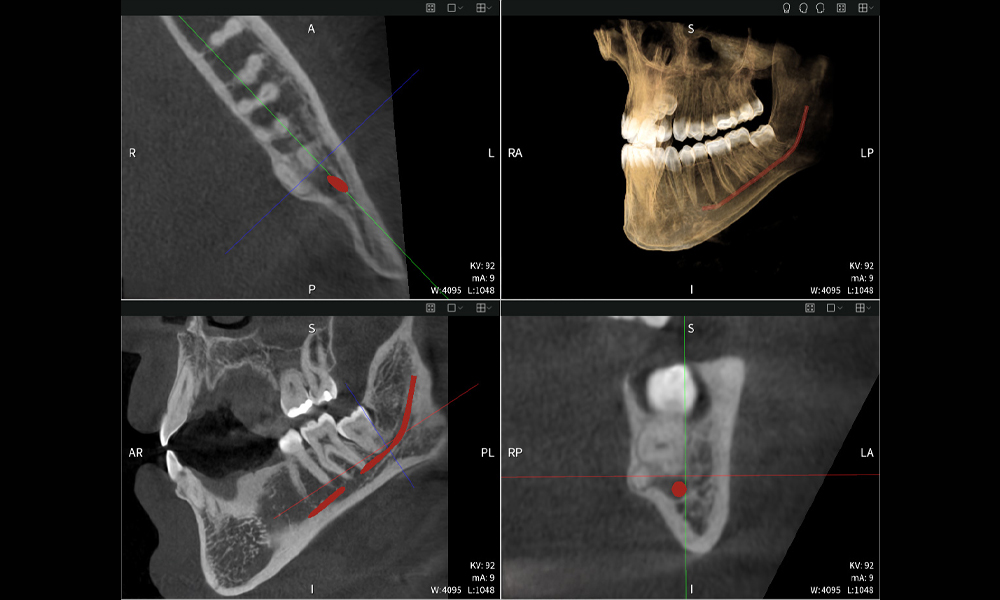

Figures b–d show various views of a 3D reconstruction of the mandible, providing a comprehensive overview of the mandibular anatomy, the position of the nerves in relation to the teeth, and allowing assessment of tooth symmetry and alignment.